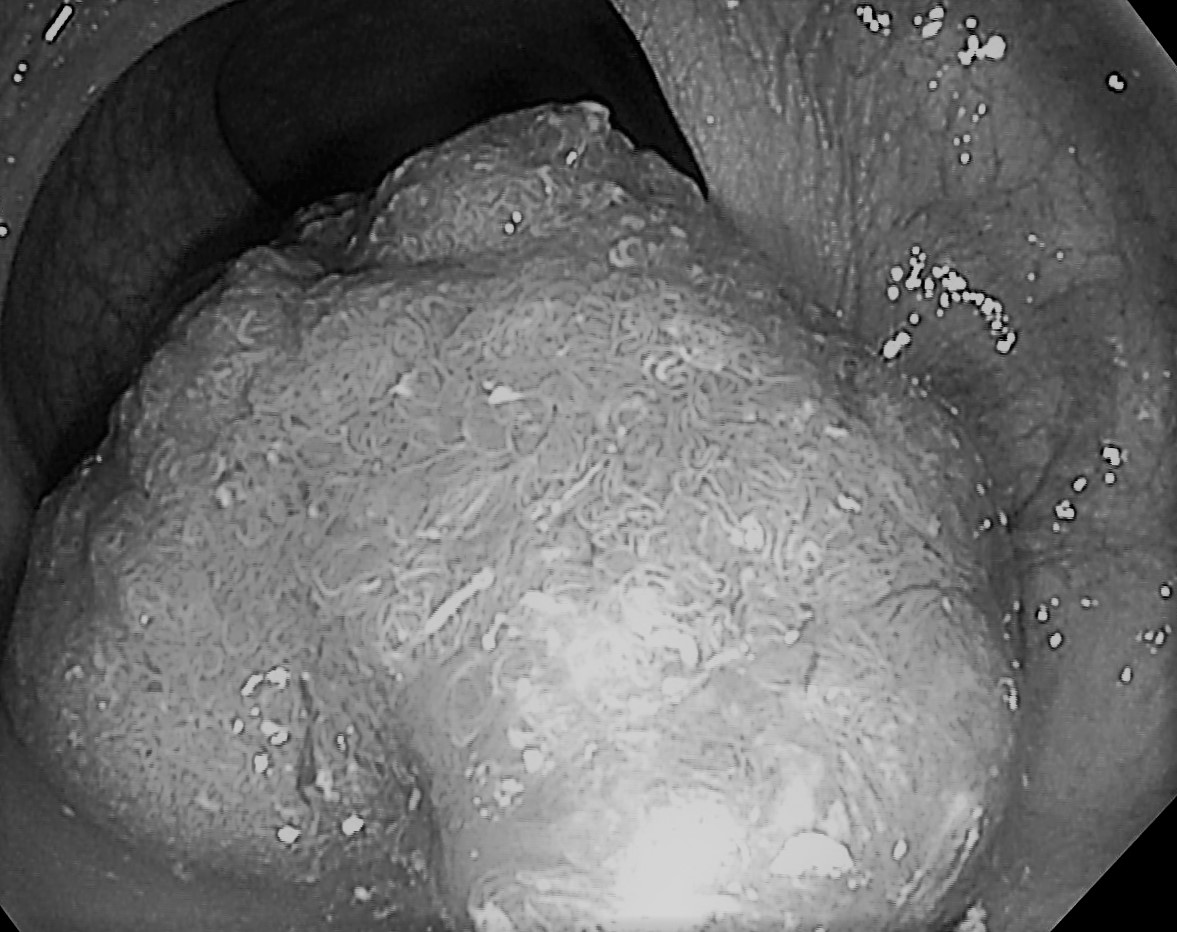

Bệnh nhân nữ 74 tuổi có tiền sử tăng huyết áp, tiền đái tháo đường mới phát hiện vào Bệnh viện đa khoa quốc tế Hải Phòng thăm khám vì đại tiện ra máu, có khối sa lồi hậu môn. Bệnh nhân được nội soi đại tràng phát hiện trực tràng thấp cách mép hậu môn 3cm có tổn thương polyp gần lấp lòng trực tràng, qua đánh giá trên hình ảnh nội soi phóng đại cấu trúc bề mặt polyp type IIa và một số vùng IIb theo JNET, định hướng là loạn sản nặng hoặc ung thư sớm có chỉ định cắt qua nội soi.

- Hình ảnh polyp “khổng lồ”